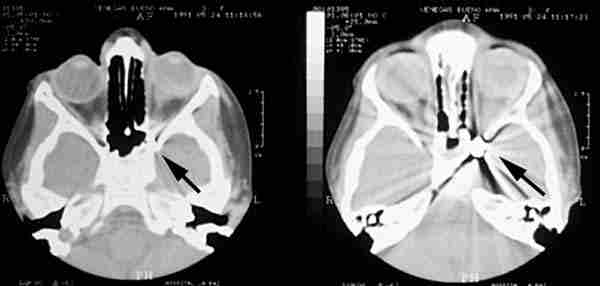

La utilización de Rayos X (figura 15) con proyecciones Caldwell, Waters, o las antero-posteriores pueden demostrarnos la presencia, pero no la localización, de un CEIO radiopaco y no detectará CEIO radiotransparentes, como la madera o el cristal. La ecografía nos ofrece una mejor localización del CEIO y es esencial para obtener información acerca de otros cambios estructurales como desprendimientos de retina o coroides. Al realizar esta exploración, han de tomarse precauciones para no comprimir el globo, sobretodo en los que presentan grandes heridas, y no producir prolapsos adicionales de su contenido. La ecografía con un estudio sistemático, con abordaje transversal y longitudinal puede determinar la localización del CEIO. La ultrasonografía biomicroscópica nos aporta algo más a la hora de diagnosticar cuerpos extraños ocultos o de polo anterior (123-125). La tomografía computerizada (TC) es el método diagnóstico de elección porque localiza y detecta CEIO radiopacos y radiotransparentes en 3 dimensiones. La TC tiene ciertas limitaciones y los CEIO metálicos crean artefactos significativos, que pueden dificultar la localización exacta. Esto puede ser un inconveniente a la hora de determinar si la localización de un CEIO es intrarretiniana o intraescleral. Asímismo la TC puede presentar problemas a la hora de identificar algunos CEIO de baja densidad, como la madera. Chacko, nos presenta en su artículo una interesante comparación entre la Tomografía Computerizada clásica (figura 16) y el TAC helicoidal (figura 17), demostrándose esta última más eficaz para la localización espacial de cuerpos extraños intraoculares o intraorbitarios (126).

63-16.jpg (11435 bytes)

Figura 16. Perdigón que pasa a través del ápex orbitario destrozando el nervio óptico.

63-17.jpg (11175 bytes)

Figura 17. La tomografía computerizada (TC) es el método diagnóstico de elección porque localiza y detecta CEIO radiopacos y radiotransparentes en 3 dimensiones.